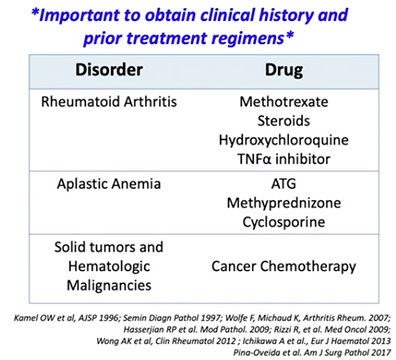

- <10% clonal plasma cells in BM